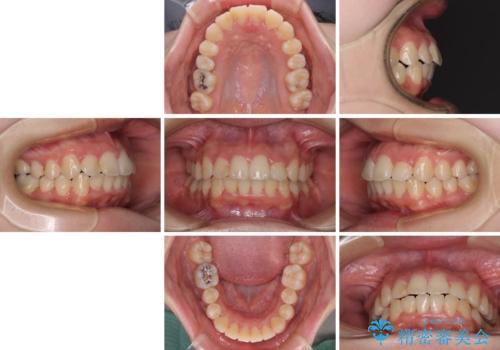

短期間で終了 デコボコをワイヤー矯正で解消

- 1年3ヶ月

- 上下のデコボコと前歯のクロスバイトを改善したいとのことで来院された患者様です。

マウスピースによる矯正治療も提案しましたが、ご自身でのマウスピースの管理の面倒くささと、なるべく早く治療を終えたいとのことで、ワイヤー矯正を選択されました。